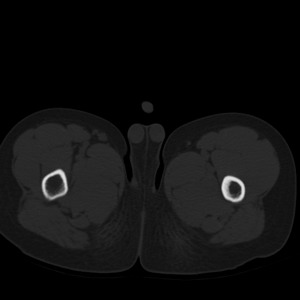

标题: PED1884:患者,男性,7岁。因右髋疼痛5天,而来院检查。 [打印本页]

标题: PED1884:患者,男性,7岁。因右髋疼痛5天,而来院检查。

因右髋疼痛5天,而来院检查。

我们考虑:1、骨皮质增厚症。2、畸形性骨炎。3、骨纤。

右髋疼痛,左侧病变,看来无症状。

支持左股骨上段骨纤维异常增殖症可能性大.